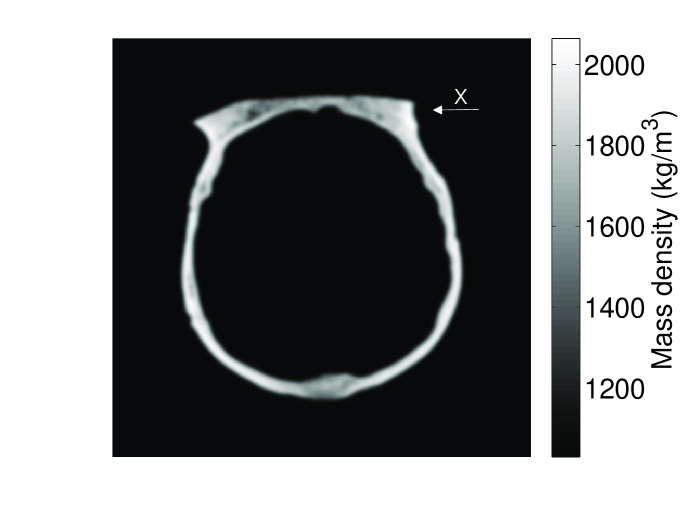

Investigation of systematic errors: The SOS and density maps employed in the simulation studies were representative of a monkey skull [10]. The dimensions of the skull were approximately 777 cm ×\times 666 cm, and its thickness ranges from 2 to 4 mm. Figure 2-(a) and (b) show a transverse slice of the SOS and density maps, which were used in the 2D simulations.

Figure 2: A slice of the SOS (a) and density (b) map deduced from the X-ray CT data of a monkey skull. Panel (c) and (d) display profiles of the SOS and density maps along the ‘X’-axis indicated in Fig. 2, respectively. Red dashed lines are the profiles of the assumed maps, whereas the blue solid lines are the profiles of maps with errors.

Since errors in the estimated SOS and density maps are inevitable regardless in how they are determined, we investigated the robustness of the reconstruction methods with respect to the SOS and density map errors, which were generated in two steps. First, 1.3% (with respect to maximum value) uncorrelated Gaussian noise with mean value of 1.7% of the maximum value was added to the SOS and density maps to simulate inaccuracy of the SOS and density values. Subsequently, the maps were shifted by 7 pixels (1.4 mm) to simulate a registration error. Figure 2-(c) and (d) show profiles of the SOS and density maps with those errors along the ‘X’-axis indicated by the arrows in Fig. 2-(a) and (b), respectively.